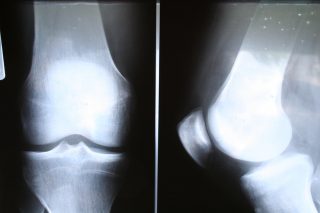

L’articolazione del ginocchio, dal punto di vista osseo, è costituita da femore , tibia e rotula.

Le due grandi ossa chiamate Femore e tibia sono ossa di grandi dimensioni che devono sostenere tutto il peso del nostro corpo, anche sotto stress fisico, mentre la rotula contribuisce al movimento di flesso-estensione del ginocchio. Tra il Femore e la Tibia sono interposti i menischi, le due ossa sono unite da robusti legamenti e l’intera articolazione e racchiusa in un rivestimento chiamato capsula articolare. I legamenti sono 4; due laterali chiamati collaterale mediale o interno(LCM)e collaterale laterale o esterno (LCL), ed altri due interni chiamati ; legamento crociato anteriore(LCA) e legamento crociato posteriore (LCP). Nella parte superiore della tibia subito sopra la cartilagine ci sono due sottili cuscinetti fibro cartilaginei, chiamati menischi ,uno mediale ed uno laterale. La patologia più frequente che riguarda il ginocchio interessa i menischi, i legamenti, in particolare il crociato anteriore e la cartilagine. I sintomi più comuni sono, il dolore articolare, la tumefazione, la rigidità e l’instabilità articolare, fino ad arrivare alla zoppia con limitazione alla deambulazione.